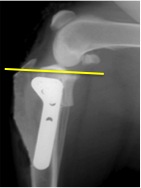

手術は様々な方法がありますが、当院ではTPLO(脛骨高平部水平化骨切術)を実施しております。 TPLOは前十字靭帯断裂に対する最新の手術法の1つです。 脛骨を一部骨切りし、回転させることによって斜めに傾いているところを平らにし、 脛骨が前に出る力を無くしてあげようという手術法です。

*

他の手術方法ではワイヤーや他の靭帯を用いて前十字靭帯の再建を試みますが、 TPLOは膝の機能の安定化を目的としている手術法です。 そのためTPLOは前十字靭帯の完全断裂だけでなく部分断裂の治療法としても有効であり、 活発に運動ができるようになるまでの期間を従来の手術法よりも短縮させ、 関節内の変化を最小限に抑えることが出来ます。 特に、長期のリハビリテーションや術後管理が困難な大型で活動的な犬の治療法として最適です。 実際に手術を行なった子のレントゲンです。斜めだった脛骨が平らになっているのが分かります。